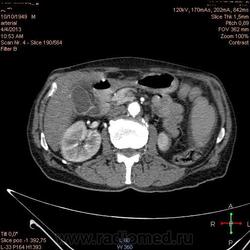

Здравствуйте, коллеги.Помогите разобраться.Пациент 1949 г беспокоять боли в животе , отсутствие аппетита, похудание .За неделю пожелтел, ослаблен.Нужно исключит кацер головки подж.железы.Анализы сегодня сдал еще не готовы.УЗИ зак увеличение л\узлов у ворот печени.Образов головки подж.железы ?На КТ жировой гепатоз.вроде головка подж железы не увеличены.

Мне надо исключить или поставить образование головки подж.железы.Хирурги ждут заключение, хотять оперировать.

А про билиарную гипертензию на УЗИ и КТ ничего не говорится?

Даже если вы пропустили малый рак панкреас, пациент умер не из-за него - желтуха не механическая, а, вероятней, паренхиматозная.